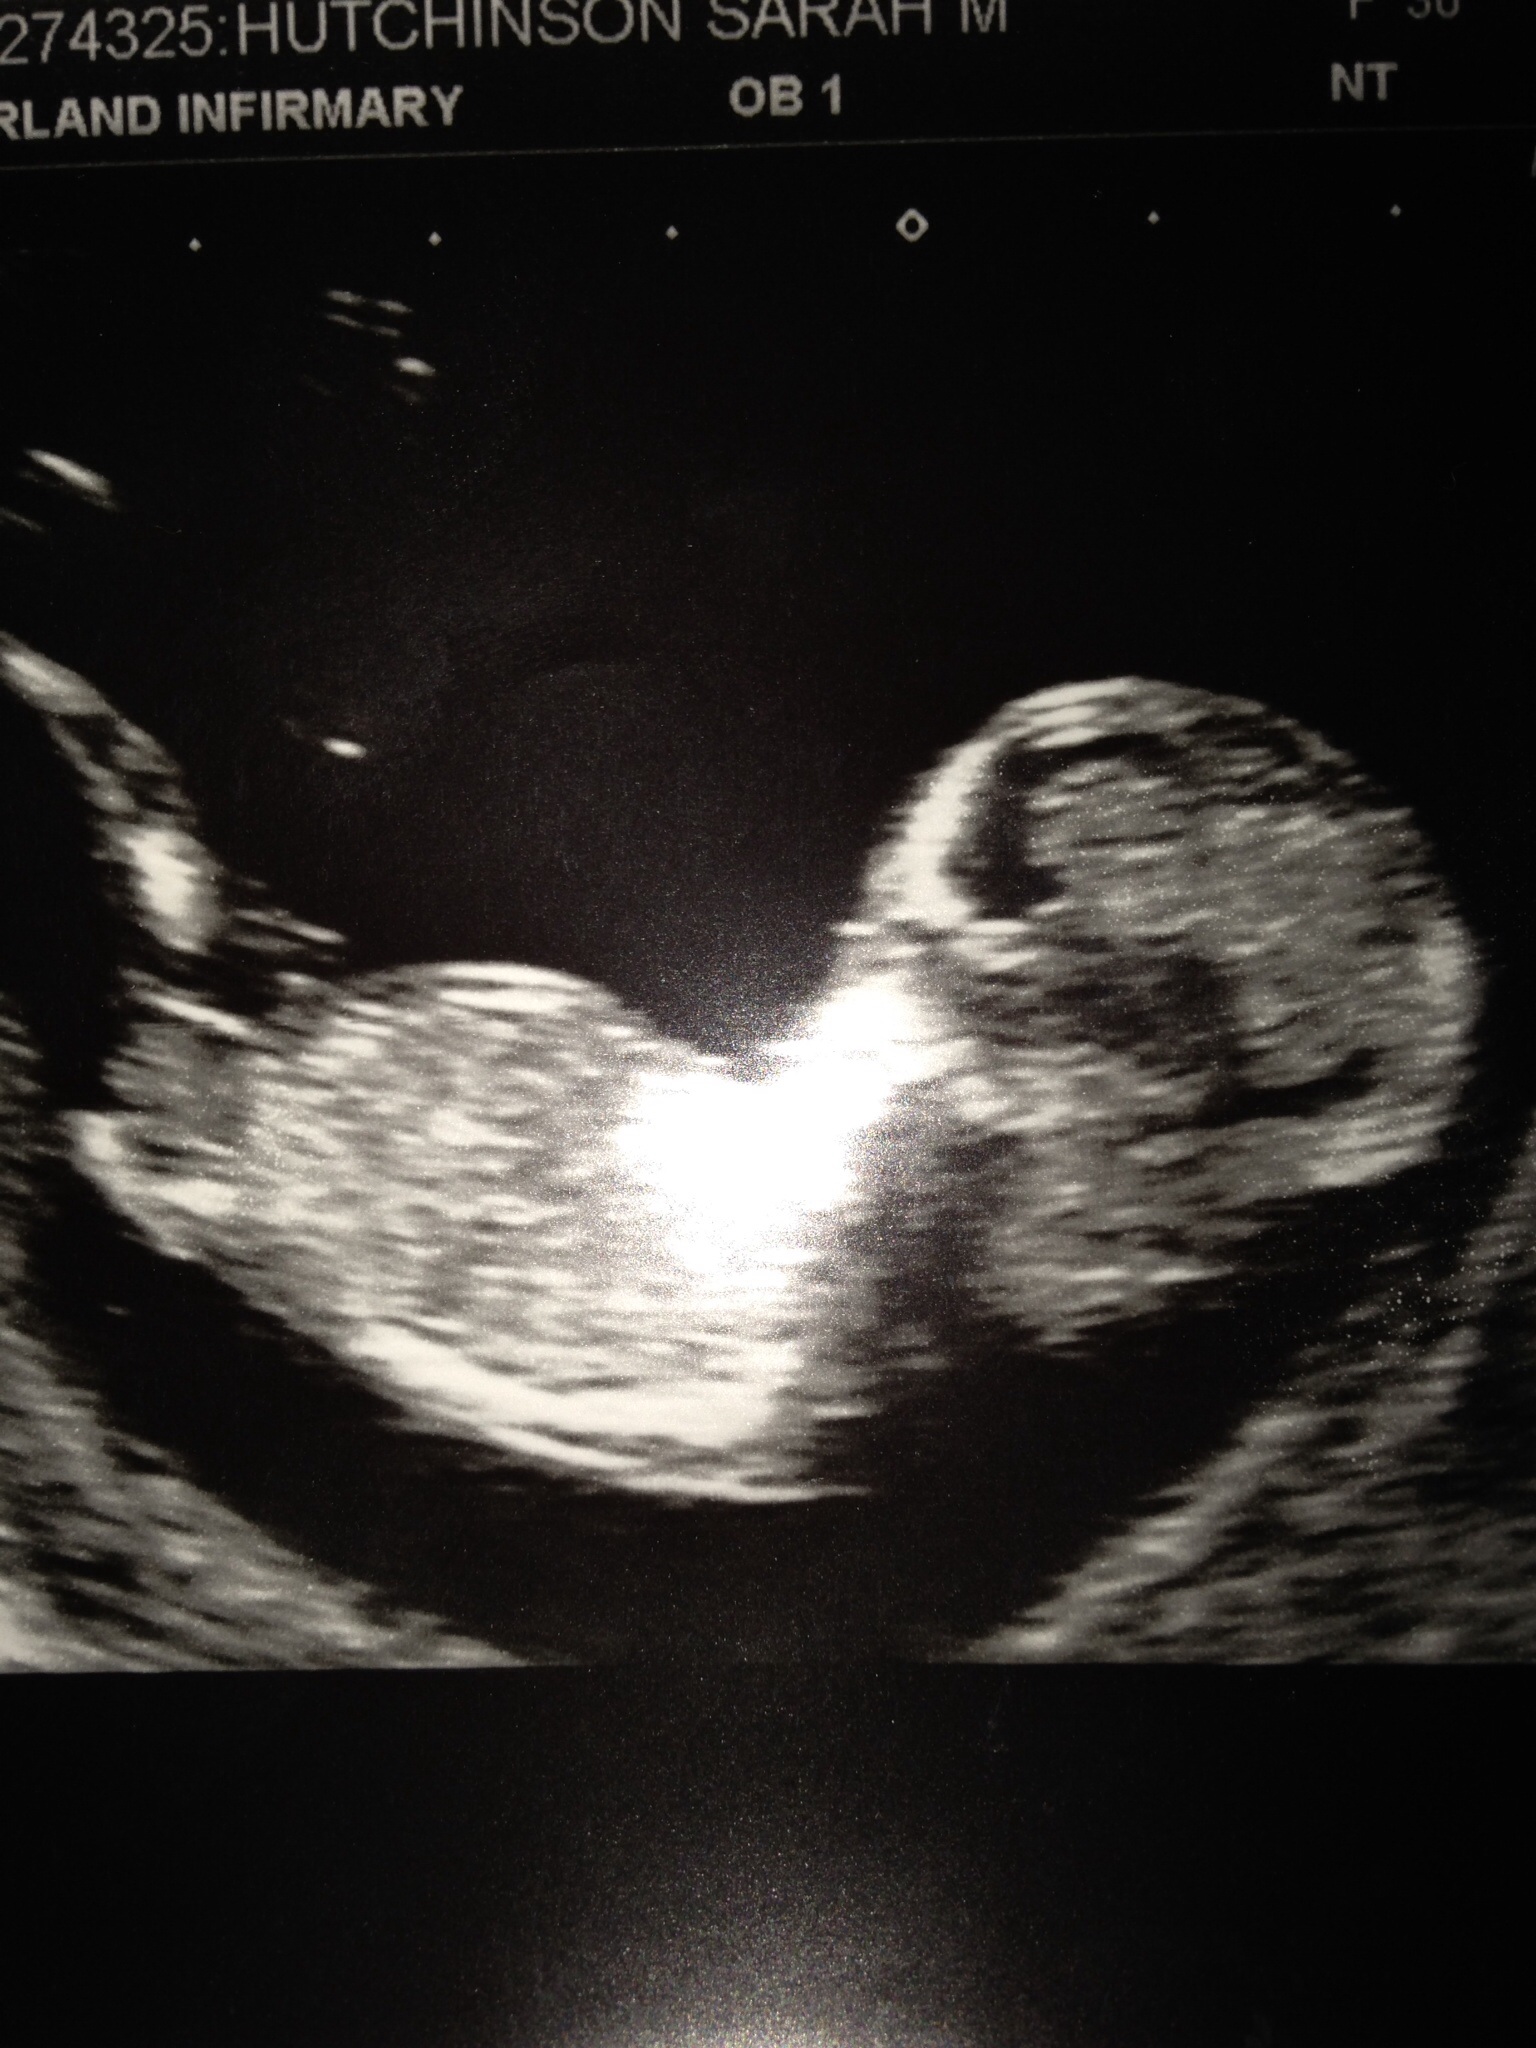

This baby is doing a back dive! Not the right angle/view.

I think it's just the way the photo was taken as the baby has it's spine to the bottom of the photo! I'm worried now!

If that's a nub I can see on ur last picture I'm going to guess girl